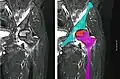

Nuclear magnetic resonance of avascular necrosis of left femoral head. Man of 45 years with AIDS.

Nuclear magnetic resonance of avascular necrosis of left femoral head. Man of 45 years with AIDS. -